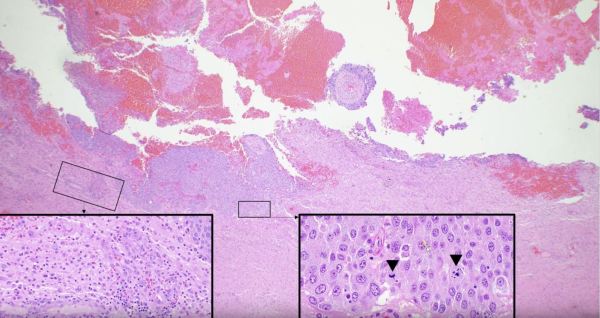

Dura Metastasis: Hepatocellular Carcinoma

The most common tumors found in the central nervous system and dura (i.e. the dense fibrous covering that envelops the brain) are those that have traveled from other body sites in a process called metastasis. Depicted here is hepatocellular carcinoma (HCC), a cancer of liver cells, that has metastasized to the dura overlying the anterior pole of the right frontal lobe. Microscopically, the neoplastic liver... Continue Reading →